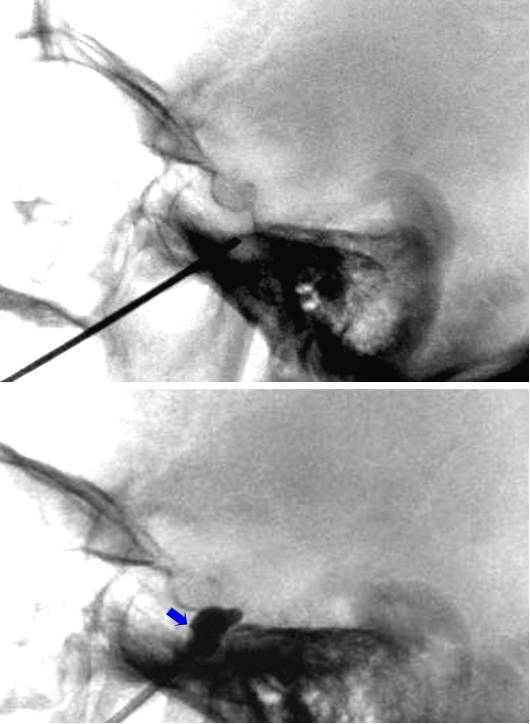

图3. 针尖靠近颅底但未穿出卵圆孔(上图),碘海醇造影剂0.5ml缓慢充盈球囊,在X线引导下,观察球囊的充盈情况。球囊位置向圆孔轻微扩展(下图蓝色箭头)。特征性的梨状外观表明球囊进入Meckel’s腔,其下方由岩骨围成,上方为硬脑膜缘。